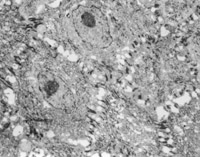

2. 電鏡觀察 受傷當日上皮組織變性壞死,可見單核細胞核偏移、固縮,并有吞噬現(xiàn)象(圖5-3-12)。

5-3-12 燒傷當日,單核細胞核偏移,固縮,并有吞噬現(xiàn)象  TE×8000